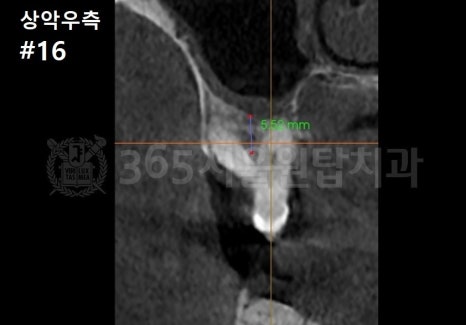

염창동 임플란트 식립 각도는 3차원 CT를 충분히 활용하여 확인하세요

염창역 임플란트 CT 설명을 위한 예시 자료입니다.

3D CT를 통해

뼈의 두께와 밀도, 신경 위치를 확인하고

최종 보철물의 형태까지 예측합니다.